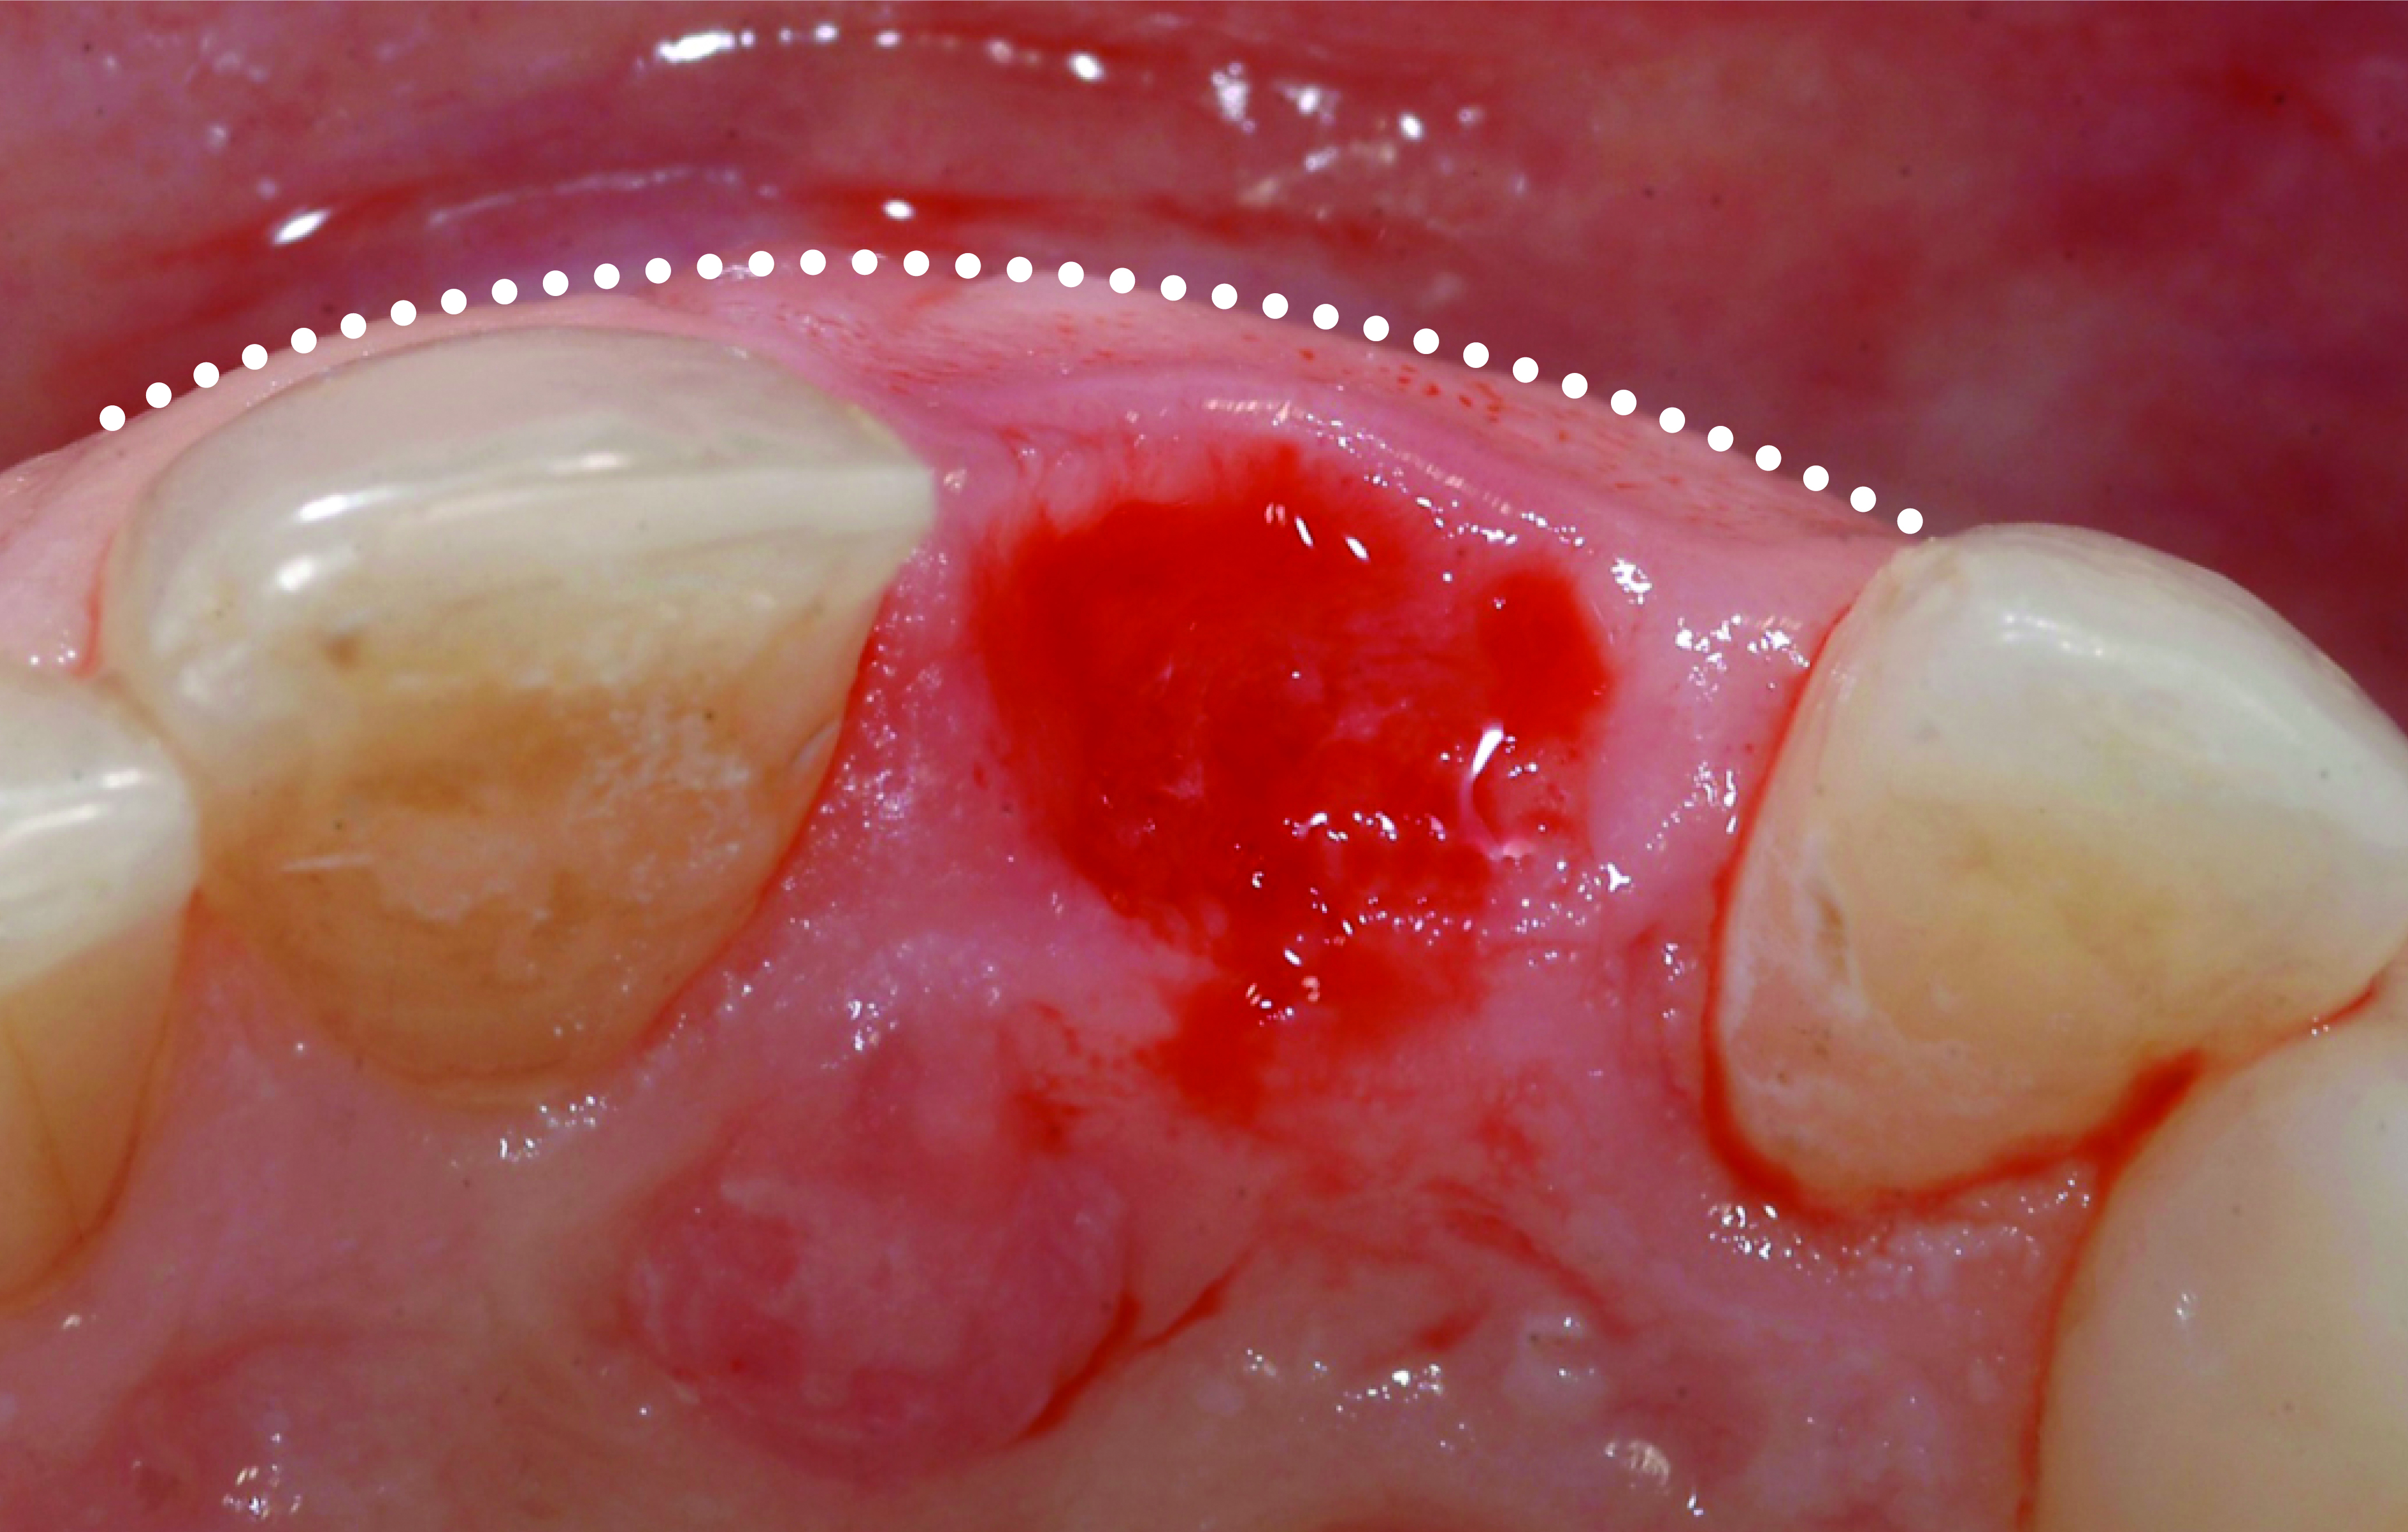

It is uncommon to find thick bone walls forming a socket in the esthetic zone, as seen in Figure 1. The buccal plate thickness in a socket is, on average, 0.9 mm +/- 0.4 mm at the mid-root area and roots are often positioned buccally in the ridge.1 As a result, ridge resorption after extraction is common and can be even more significant when the walls of the socket are affected by dehiscences or fenestrations (Figure 2). Although facial ridge resorption is more common, some degree of vertical resorption is also expected after an extraction; both become more significant when more than one tooth is extracted.2-4 Ridge preservation procedures can minimize the degree of post-extraction ridge remodeling through the addition of a variety of bone graft materials at the time of extraction. Figure 3 clearly illustrates moderate buccal ridge resorption that develops post-extraction, while Figure 4 shows little remodeling as a result of placement of an allograft at the time of extraction.

Fig 2. Thin facial bone. Facial fenestrations as illustrated or dehiscences are common over incisors and cuspids in the pre-maxilla and increase the complexity of implant treatment; they potentially increase the risk for long-term post-restoration tissue instability.

Figure 2

Fig 3. Facial bone resorption resulting in loss of tissue contour is common where ridge preservation was not incorporated into the extraction procedure.

Figure 3